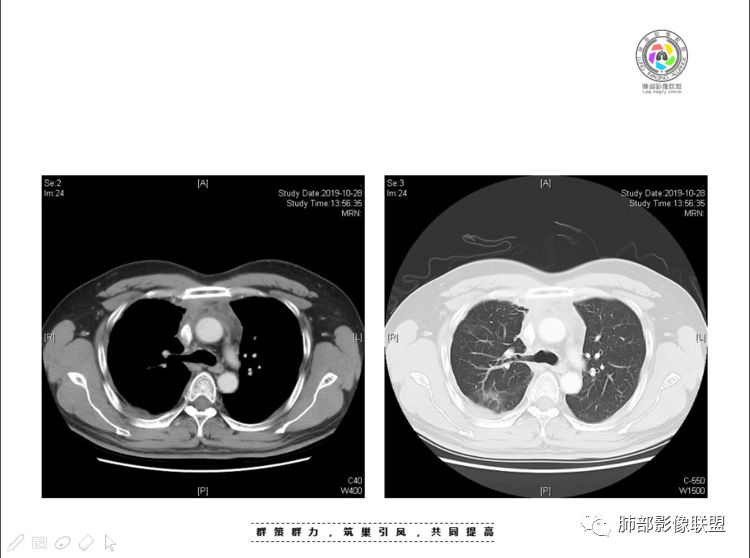

穿越七海的风:右前纵隔占位,恶性肿瘤,生殖来源?右肺实变是占位or肺不张?考虑为部分肺不张FeNo:右前纵隔占位,右肺结节,胸膜凹陷,小尾巴,右肺不张,考虑恶性杨旭华:恶性,前纵隔肿物,与血管关系密切,上腔静脉变窄,右肺野一元论考虑叶间裂增厚,恶性胸膜间皮瘤可能大小丽:到底是纵隔来源还是胸膜来源?我怎么倾向于胸膜来源,和叶间胸膜关系密切,而且纵隔内上腔静脉是向内侧推移。胸膜肿瘤(间皮瘤?SFT?)包裹性胸腔积液?马春平(张家港市一院胸外科):前纵隔占位,左无名受压,右大量胸腔积液可能是胸导管汇入处侵犯受压,考虑纵隔鳞癌孙冰伟:右上纵隔占位,也感觉和叶间胸膜关系密切,右侧胸膜局限性增厚,考虑恶性可能性大灵:前纵隔占位,血性胸水,胸膜凹凸不平,查见肿瘤细胞,结合免疫组化考虑胸腺癌。鉴别胸膜间皮瘤。采莲:右前上纵膈旁可见类圆形肿块,纵隔血管内移,感觉来源于胸膜,肿块内密度低,似水样密度,右侧胸膜广泛增厚,少量胸腔积液。心包少量积液。考虑胸膜间皮瘤,鉴别肺癌并胸膜转移?水晶石头:患者中年男性,胸闷15天。有“高血压、慢性肾小球肾炎”病史。查肿瘤标志物正常,胸水提示渗出液,胸水病理查见瘤细胞。胸部CT:右肺上叶后段结节、斑片影,见胸膜牵拉、包裹积液及部分纤维条索灶,似见卫星灶,右侧胸膜增厚。前纵隔脂肪密度增厚,右侧可见类圆形低密度(液体)肿块,边缘光滑。综合考虑右肺腺癌并胸膜转移,结核可能。周太狼:考虑纵隔胸膜来源肿瘤,恶性,胸膜间皮瘤伴转移?徐飞:中年男性,影像为右侧胸腔及叶间积液,叶间胸膜增厚轻度强化。前纵隔右侧心缘旁团块,可见坏死。胸水见癌细胞,综合考虑恶性,胸腺癌伴转移。小赵:中年男性,血性胸水,常规查见癌细胞,李凡他实验阳性。胸部CT示前纵隔见不均匀密度影,与邻近大血管分界不清,囊变坏死明显,增强扫描呈不均匀强化,心包及右侧胸膜增厚,并心包及右侧胸腔少量积液。综合考虑胸腺癌。右肺中叶病变周围见多发纤维条索,支气管部分进入病灶,考虑炎性病变。流心明智:患者,男性,50岁。胸闷15天。高血压20年,慢性肾小球肾炎15年。肿标正常,胸水提示渗出液,胸水查见癌细胞。胸部CT:右肺肿块影,斑片影,索条影,可见胸膜牵拉、多发包裹积液,纵隔上腔静脉受累,心包受累。综合考虑:ROSE似腺?考虑右肺腺癌并胸膜转移,心包受累。鉴别胸腺Ca、淋巴瘤,纵隔病变不懂,等老师们精彩分析。王秀仙:前纵膈囊实性肿块,与纵膈分界不清,心脏大血管及上腔静脉受压向内后移,右侧后胸膜、侧胸膜增厚,右侧叶间裂不规则增厚,心包积液,根据腔静脉移位情况,考虑纵膈胸膜来源恶性肿瘤,胸膜间皮瘤?鉴别胸腺癌并胸膜转移。高广飞:上纵隔占位,右侧叶间胸腔积液,需考虑恶性自信人生:多发囊实性病灶,包裹性积液,考虑胸膜来源 只是没有看到壁结节,恶性胸膜间皮瘤巴伟:前上纵隔占位,胸膜及心包结节,考虑胸腺瘤或癌,右肺病灶,先考虑陈旧炎性病变。Lenle董:前纵隔占位,部分边缘模糊,病灶内囊变?坏死?上腔静脉受侵,考虑胸腺癌;叶间片状影,强化明显,炎性考虑。常志强:前纵隔囊实混杂密度肿块,边界不清,实性部分强化明显,结合胸水内见癌细胞,考虑恶性肿瘤伴转移。飞鹰行动:前纵隔占位,软组织密度及囊性密度,实性部分密度均匀,致密,病灶与周围血管分界不清,增强后病灶强化有类似不温不火强化,部分血管受侵犯,右肺见肿块样病变及条索状病变,一元论,考虑淋巴瘤,二元论,考虑胸腺瘤B2—B3伴右肺病变。尽量一元论考虑,淋巴瘤可能。看图说话:右肺索条病灶,边缘膨隆,胸膜牵拉,考虑右肺癌伴胸膜转移。晨:前纵隔囊实性肿块,与纵隔分界不清,右侧后胸膜、侧胸膜增厚,右侧叶间裂不规则增厚,考虑纵隔胸膜来源恶性肿瘤,考虑胸腺癌并胸膜转移。丽:中年男性,前纵隔囊实性肿块,呈偏心性生长,临近大血管受压推移,增强后实性部分不均匀强化,心包可见条形积液,考虑胸膜来源恶性肿瘤,胸腺癌可能大。另右肺多发斑片状高密度影及实变密度影,实变影呈均匀强化,右侧胸膜局限性增厚,考虑炎性病变。小飞:右前纵隔囊实性占位,实性部分明显强化,右侧叶间胸膜增厚,右侧胸腔积液,心包积液,考虑恶性胸腺瘤!尘缘:支持恶性胸腺瘤(囊实性肿块,实性强化,且侵犯纵隔,脂肪间隙模糊)伴肺内及胸膜转移。浪迹天涯:考虑侵袭性胸腺瘤——胸腺前纵隔占位,周围脂肪间隙模糊不清。尘缘:不除外另一种可能:二元,肺内腺癌合并胸膜转移,纵隔的畸胎瘤可能。一米阳光:晨读中年男性,右肺结节影,叶间裂及胸膜增厚牵拉,右侧胸水。心包多发结节改变。胸水查见癌细胞。考虑,腺癌并转移。鉴别,胸膜间皮瘤并转移前纵隔囊实性占位,二元考虑。心灵鸡汤:老年男性,右肺中叶外段长条状软组织密度影,边缘膨隆,邻近胸膜牵拉,部分胸膜有栽脏,右中叶外侧段支气管堵塞,常规考虑恶性肿瘤,腺癌可能,结核、鳞癌不除外,另右肺上叶斑片影,小叶性肺不张?右前纵隔囊实性不规则形密度影,其内见部分脂肪样极低密度影,与邻近血管边界不清,心包外膜有侵犯,增强未见纵隔窗平扫,实性及分隔见增化,其内低密度影未强化,考虑低度恶性纵隔肿瘤,间皮瘤可能,畸胎瘤、淋巴瘤待排,建议支气管镜及穿刺活检。曹志勇:右前纵隔考虑来源于胸膜的恶性肿瘤,右肺内病灶考虑鳞癌,二元德芙~云味:中年男性,右肺见结节、斑片影,右侧包裹积液、胸膜牵拉,纤维条索,前纵隔囊性占位,考虑腺癌、并转移。欧阳英:右前中纵隔囊实性肿块及右肺内结节灶,支持恶性肿瘤,胸腺癌并肺内转移可能张延军:前纵隔见不规则软组织影,密度不均,右侧缘见囊变区,纵膈及侧胸壁胸膜增厚,增强呈不均匀强化,右肺中叶见结节灶,近段支气管阻塞,叶间胸膜不规则增厚,考虑1:右肺中叶腺癌伴纵膈及胸膜转移;2:前纵膈侵袭性胸腺瘤并胸膜侵犯,中叶炎性改变?彭君:老年,前纵隔占位 ,坏死边缘清, 侵犯心包 右侧胸膜及叶间胸膜结节 ,少量胸水, cea不高 ,考虑恶性, 间皮瘤可能 ,转移待除外。毛勤香:恶性没问题,胸水查见癌细胞,一元还是2元,右肺中叶肿块,边缘毛糙,局部似有毛刺,周围有粘连,右侧胸膜腔少量积液,胸膜增厚多发结节,含叶间裂结节,纵膈脂肪间隙模糊,纵膈胸膜增厚,心包增厚积液,右前那个类圆形低密度肿块,纵膈血管内移,我考虑胸膜来源可能性大,综合考虑,一元肺腺癌并多发转移,二元考虑胸膜间皮瘤并多发转移,肺内炎症不张。

肺内结节,近端支气管堵塞狭窄

整体边缘收缩,部分膨隆

炎性要考虑,但恶性不能排除

1、右肺内病灶,病灶呈结节样,边缘欠规则,局部膨隆,叶间裂胸膜牵拉凹陷,再看相应支气管腔堵塞截断,临床资料胸水中查到癌细胞,均提示病灶倾向恶性,腺癌的病理意见与之相吻合。

黄勇老师总结,腺癌如果与胸膜、叶间裂紧贴或伴胸膜凹陷,胸膜、叶间裂多发结节,应当高度怀疑腺癌转移。

胸腺瘤/胸腺癌:病灶内那么大的囊,常规考虑B型以上胸腺瘤,囊内有分隔影,病灶周围脂肪间隙模糊,常规考虑侵袭性胸腺瘤或胸腺癌,若侵袭性胸腺瘤,常侵犯胸膜、心包,很少累及肺。胸腺癌易侵犯胸膜、肺并纵隔淋巴结及远处转移。但肺内腺癌形态更符合原发灶。胸膜及叶间裂转移则即可来自肺,也可来自胸腺癌。

尽管前纵隔病灶缺乏相关病理资料,但是小编还是认为肺内与纵隔病灶以二元论解释。只是肺内恶性病灶引发的胸膜改变可能会影响我们对纵隔病灶的判断。